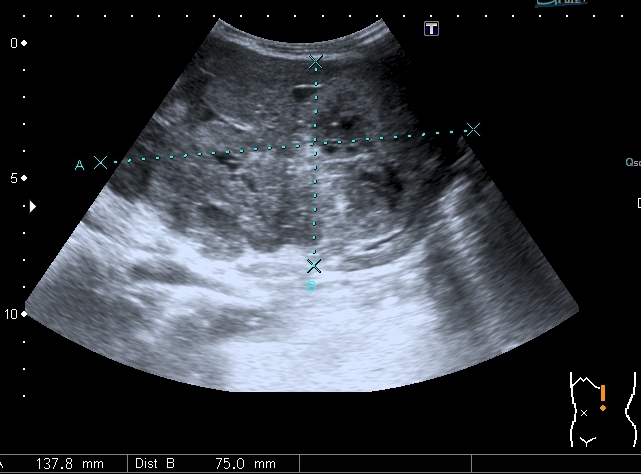

Предлагаю интересные изображения, полученные при сканировании лёгких через межрёберные промежутки и печень у ребёнка 4-х лет с подозрением на пневмонию

участок безвоздушной легочной ткани....похож на печень...пневмония в стадии опеченения... ;)

Согласен в отношении нижней доли правого лёгкого, изменения в ней похожи на сливную инфильтрацию при пневмонии, хотя носят несколько многоузловой характер. Но то что мы видим со спины в левом лёгком на пневмоническую инфильтрацию не похоже.